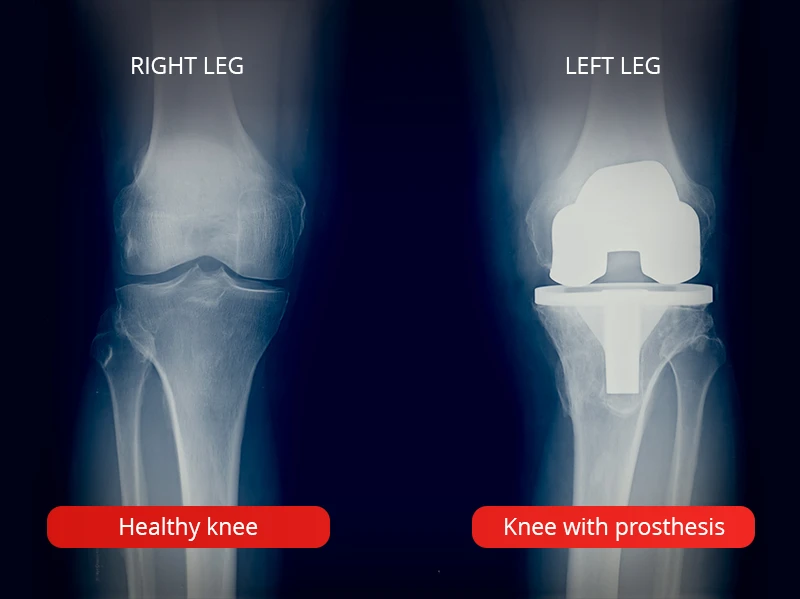

Representative image for total knee replacement surgery.

What a healthy knee and a knee with a prosthesis look like